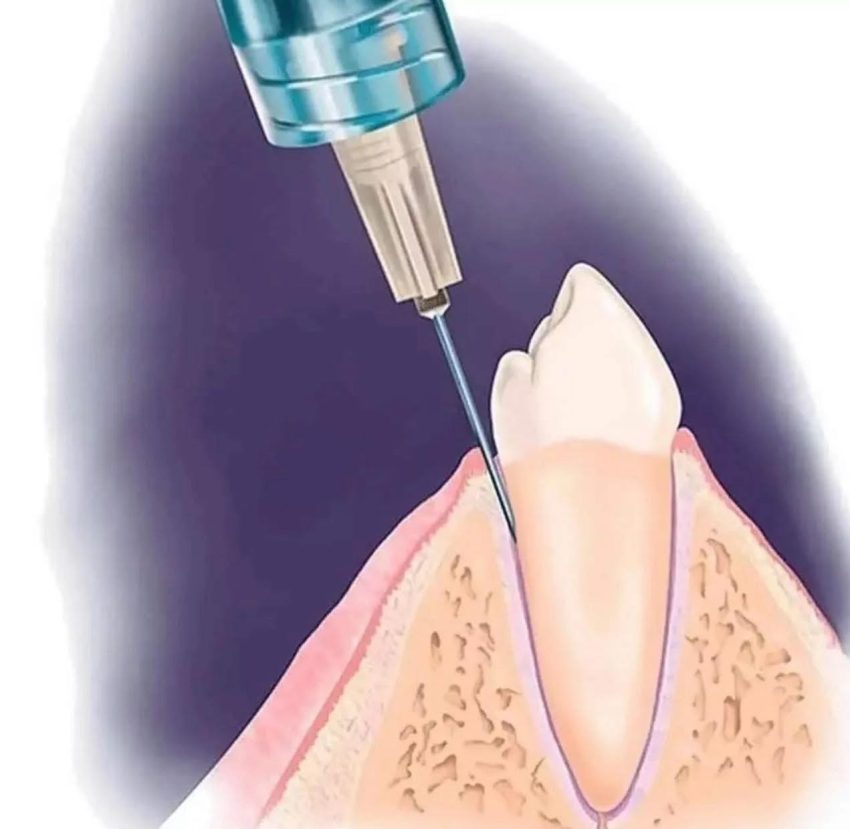

Gây tê dây chằng (hay còn gọi chính xác là gây tê nội dây chằng – Intraligamentary Injection – ILI) là kỹ thuật gây tê tại chỗ bằng cách đưa thuốc trực tiếp vào dây chằng nha chu và vùng vi xương xốp quanh răng, cho hiệu quả nhanh và phạm vi gây tê khu trú.

- Vị trí đặt kim: Mình luôn cố gắng đưa kim vào khe dây chằng ở góc khoảng 30 độ so với trục răng, mặt vát của kim hướng về phía chân răng. Kim phải đi sâu xuống cho đến khi cảm thấy lực cản của xương.